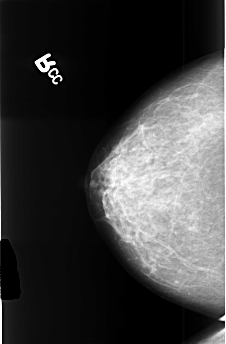

B_3477_1.LEFT_CC

LEFT_CC LINES 4440 PIXELS_PER_LINE 2920 BITS_PER_PIXEL 12 RESOLUTION 50 OVERLAY